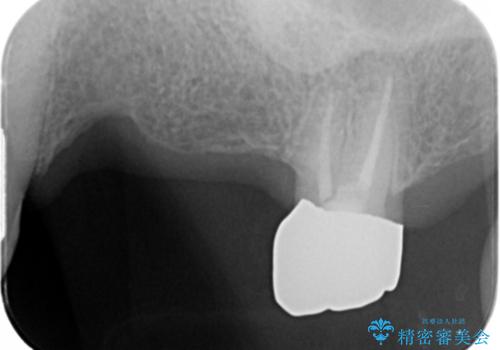

- 奥歯を失い半年間入れ歯を使用してみたが、とにかく咬めない、食事を楽しむことができない!と

咬合機能の回復を求めて来院されました。

しっかりとまた物を噛めるようになるために、インプラントを用いて咬合機能を回復していきます。

- 106.7万円(インプラント×2・チタンカスタムアバットメント×2・ジルコニアクラウン×3・仮歯×3)費用は治療当時の料金となります